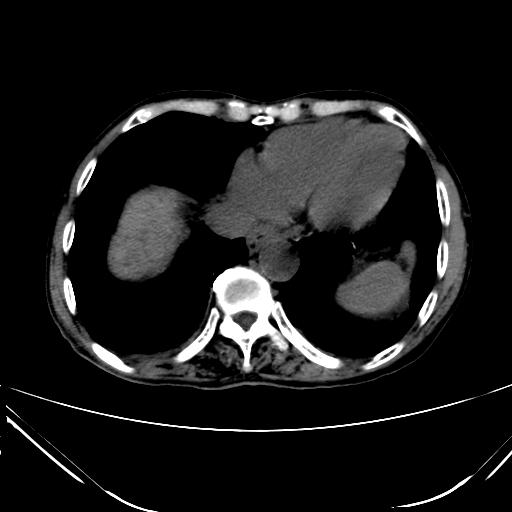

CT50427:男,76岁,B超示肝硬化,肝内占位,请会诊。多谢!

本帖最后由 cefcmj 于 2015-5-12 17:28 编辑 男,76岁,B超示肝硬化,肝内占位,请会诊。多谢!

1、肝脏多发低密度灶,建议增强扫描进一步明确诊断。

2、肝硬化、腹水、脾大。

3、胆囊炎、胆结石。

1、肝脏多发低密度灶,肝癌伴肝内转移可能,建议增强扫描进一步明确诊断。

肝硬化、腹水,胆囊结石,肝内胆管细胞癌。

肝硬化、腹水,胆囊结石,肝癌。